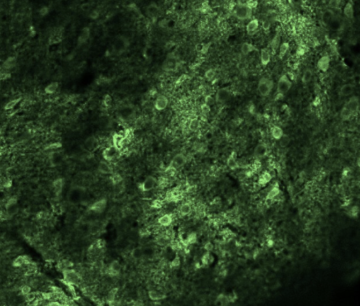

Using Immunohistology to Investigate Cholinergic Fiber Density across Layers in the Medial Entorhinal Cortex

Investigated how acetylcholine-releasing neurons connect to different layers of the medial entorhinal cortex—a brain region critical for spatial navigation and memory—using immunohistology and confocal microscopy in mice.